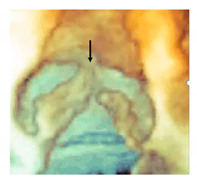

3.8. Leaflets